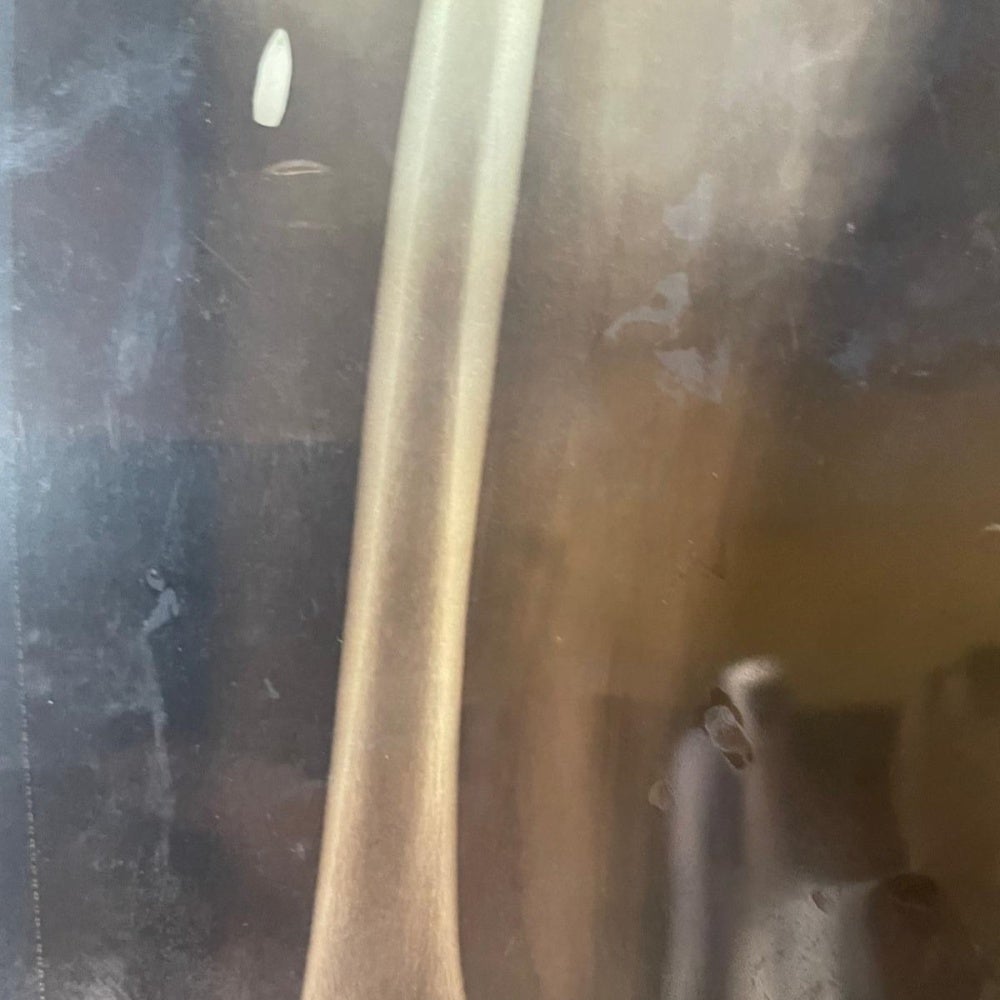

The x-ray image of a 13-year-old girl who was struck in the hip by a stray bullet in the Morsal neighborhood, N’Djamena, on May 9, 2024 following the announcement of of the provisional results of the Chad presidential elections. © 2024 Private

The x-ray image of a 17-year-old girl who was struck in the leg by a stray bullet in the Diguel Riad neighborhood, N’Djamena, on May 9, 2024 following the announcement of the provisional results of the Chad presidential elections. © 2024 Private